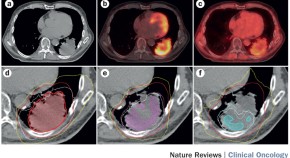

PET has evolved from a purely diagnostic imaging technique to a multifunctional modality that can provide diverse information of relevance to oncological management. This modality might offer the potential to improve patient care and outcomes by enabling better disease characterization, treatment-response monitoring, and follow-up assessment. Herein, the authors discuss the data supporting the use of PET in personalizing the clinical management of patients with locally advanced and metastatic non-small-cell lung cancer.